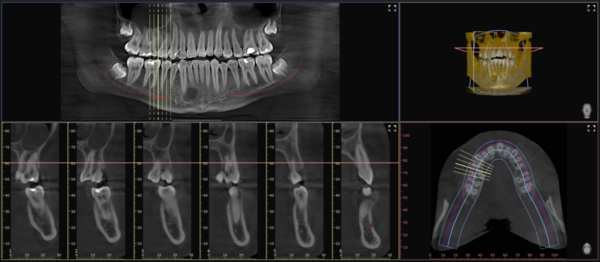

Il software VistaSoft, in sinergia con la CBCT VistaVox S, appena eseguito un esame volumetrico, ricostruisce una vista Panorex perfettamente a fuoco su due linee distinte, una per le radici e le corone, e l’altra per il profilo osseo (esclusiva Dürr Dental), permettendo al clinico di analizzare subito la corretta visualizzazione del caso. Inoltre, sempre tramite l’algoritmo della rete neurale, traccia il decorso del nervo alveolare inferiore, con un livello di precisione superiore al 98%. Al clinico non resta che verificare l’operato dell’intelligenza artificiale e dedicare il suo prezioso tempo all’analisi del caso e alla risoluzione del quesito diagnostico.